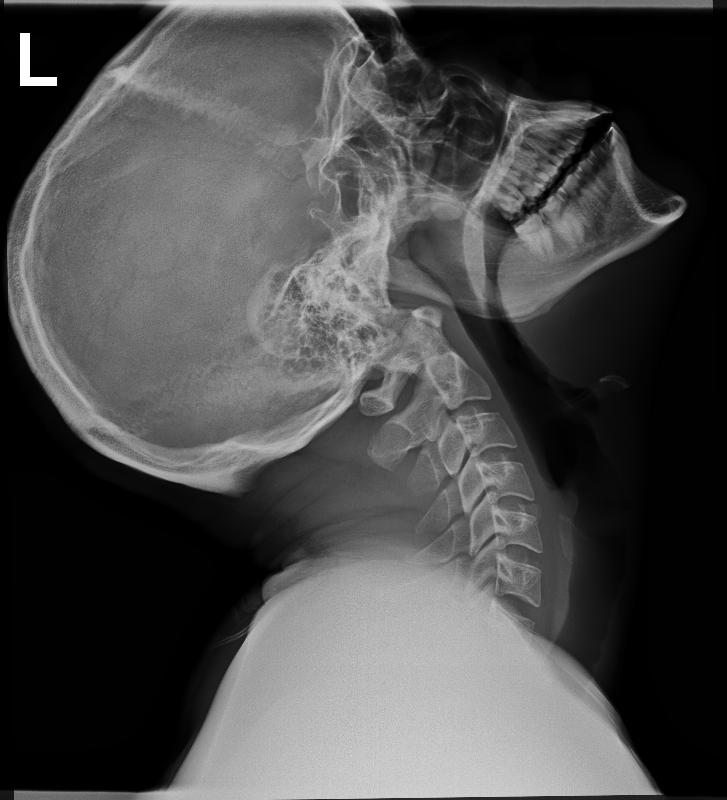

We will conduct a thorough physical examination, checking the affected area for bruising, swelling, and tenderness, as well as assessing your muscle strength, reflexes, and flexibility. To ensure an accurate diagnosis, we may utilize advanced imaging techniques such as X-rays. These imaging tools allow our team to evaluate the condition of your bones, joints, and connective tissues, and pinpoint the exact cause of your discomfort.